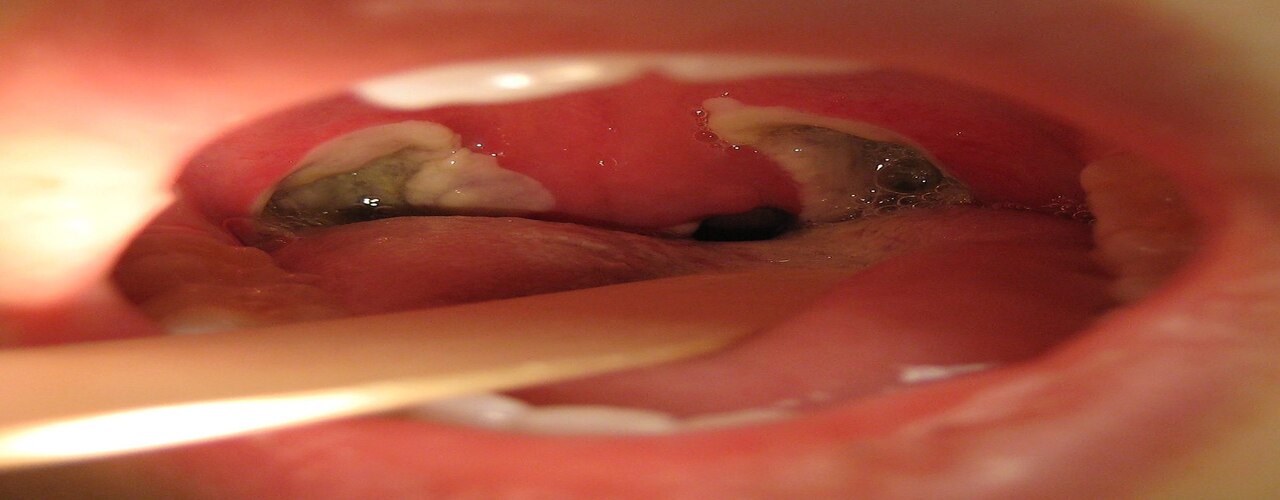

Tonsillitis poses a risk to one's throat and causes inconvenience to a person. This medical condition leads to

infected or swollen tonsils that cause difficulty eating and drinking. Surgical removal of the tonsils is the

most befitting method to evade inconvenience due to pain.

The process of surgical removal of the tonsils is called a tonsillectomy. Earlier, tonsillectomy helps to treat

tonsils that cause inflammation due to infection.